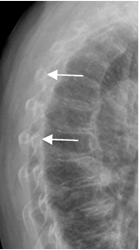

Fig 6. Costillas normales.

Rx PA. Arcos posteriores horizontales (Flechas delgadas) y arcos anterioresoblicuos, que se articulan al esternón mediante el cartílago, no visible en la Rx. (Flechas gruesas).

Fig 7. Costillas normales.

Rx lateral. Imágenes redondeadas que corresponden a los arcos posteriores., en la Rx lateral.